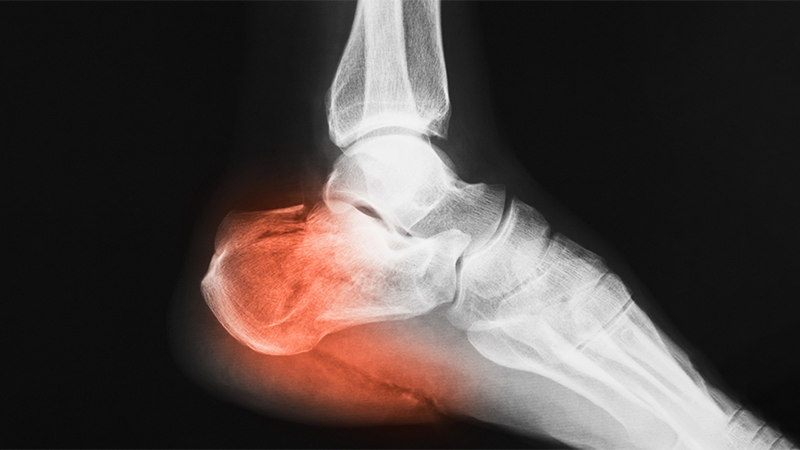

• Закрытая репозиция при переломах нижних конечностей.

Закрытая репозиция при переломах нижних конечностей.

2022-12-08

Закрытая репозиция является минимально инвазивной техникой, которую можно использовать при стабильных переломах конечностей без потери кровотока, риска инфицирования, быстрого функционального восстановления, значительного снижения медицинских затрат, а также для закрытой репозиции полым гвоздем и интрамедуллярной фиксацией штифтом. лечение различных нестабильных переломов, таких как переломы шейки бедра, переломы ножки бедра, переломы большеберцовой кости, переломы ножки плечевой кости и др., устранение нарушения кровотока путем инцизионной редукции.